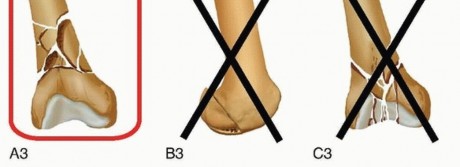

Classifications and Relative Indications It is important to assess the extent of the fracture both proximally and distally with proper radiographs. Proximally, CT scans can supplement plain radiographs to determine fracture line extension into the peritrochanteric region and to check for occult femoral neck fractures. Distally, CT imaging is helpful to assess intra-articular extension and to check for coronal plane fractures. 17 All femoral shaft fractures, as classified by the Winquist system, 33 are technically suitable for retrograde femoral nailing ( FIG 3).  ---

---  FIG 3 • Winquist femoral shaft fracture classification system.33 All fracture patterns in this system are amenable to retrograde femoral nailing.

FIG 3 • Winquist femoral shaft fracture classification system.33 All fracture patterns in this system are amenable to retrograde femoral nailing.